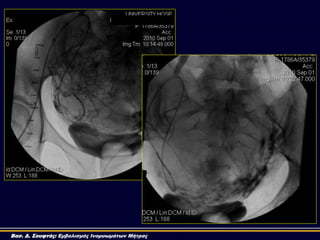

40o LAO 40o RAO

40o LAO

40o RAO

Τεχνική UAE